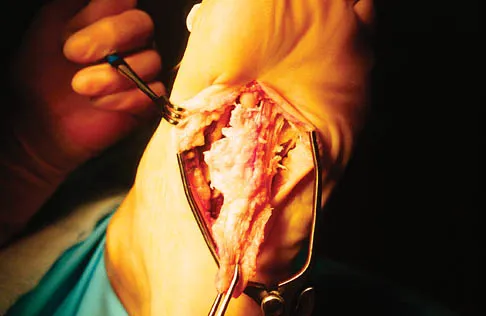

Question 35

A 56-year-old woman has a painful mass on the bottom of her left foot, and orthotic management has failed to provide relief. Examination reveals that the mass is contiguous with the plantar fascia. An MRI scan shows a homogenous nodule within the plantar fascia. Resection of the tumor is shown in the clinical photograph in Figure 39. What type of cell is most likely responsible for the formation of this tumor?

Explanation